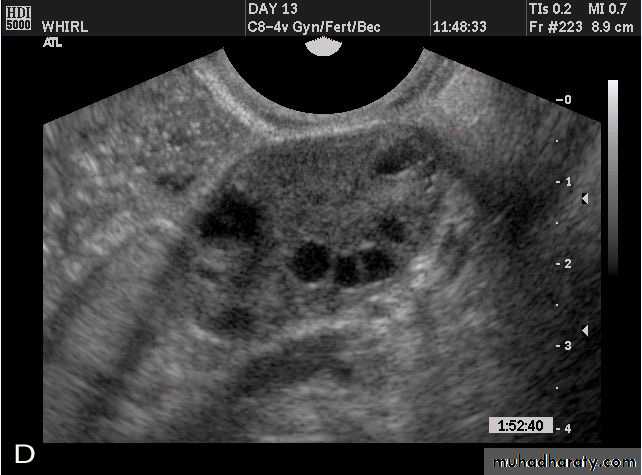

• POLYCYSTIC OVARY SYNDROME

Images from women with differing expressions of the four major subtypes of the metabolic syndrome associated with polycystic ovary syndrome (A–D). The images exhibit quite differing ultrasonographic appearances in the size and distribution of follicles within PCOS ovaries. A recent corpus luteum is clearly visible in the ovary in panel (D).